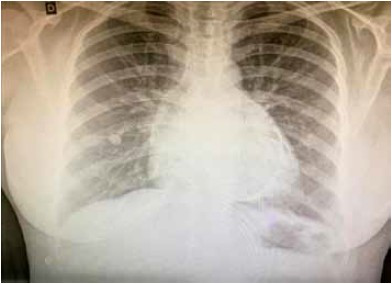

Paciente do sexo feminino, 43 anos, procura o pronto-socorro com queixa de dor torácica há 1 semana, do tipo pontada, retroesternal, sem irradiação e de caráter progressivo e contínuo, evoluindo com dispneia aos esforços há 2 dias. Sem comorbidades prévias e sem uso de medicações contínuas. Realizou a radiografia de tórax a seguir.

Ao exame físico, qual sinal clínico pode ser encontrado diante da suspeita clínica?